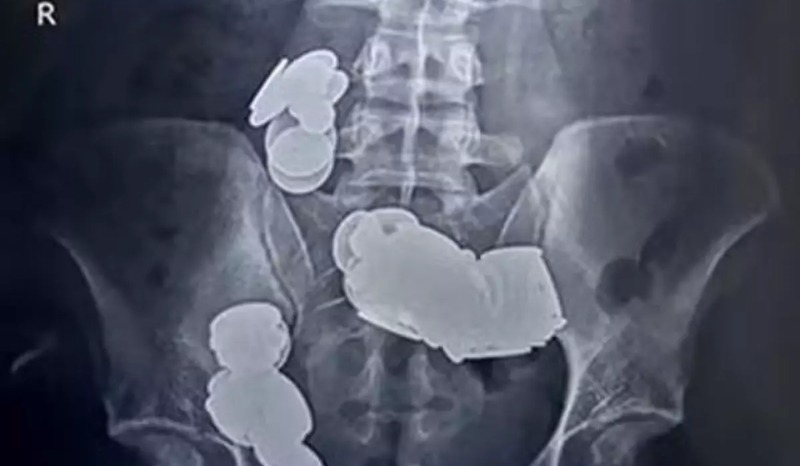

Um homem, que não teve o nome revelado, precisou passar por uma cirurgia no intestino após engolir 39 moedas e 37 ímãs acreditando que ao ingeri-los ajudaria na musculação.

O homem foi levado ao pronto-socorro com queixas de vômitos persistentes e dores abdominais que já duravam mais de 20 dias. A família dele revelou que nas últimas semanas ele vinha consumindo moedas e ímãs.